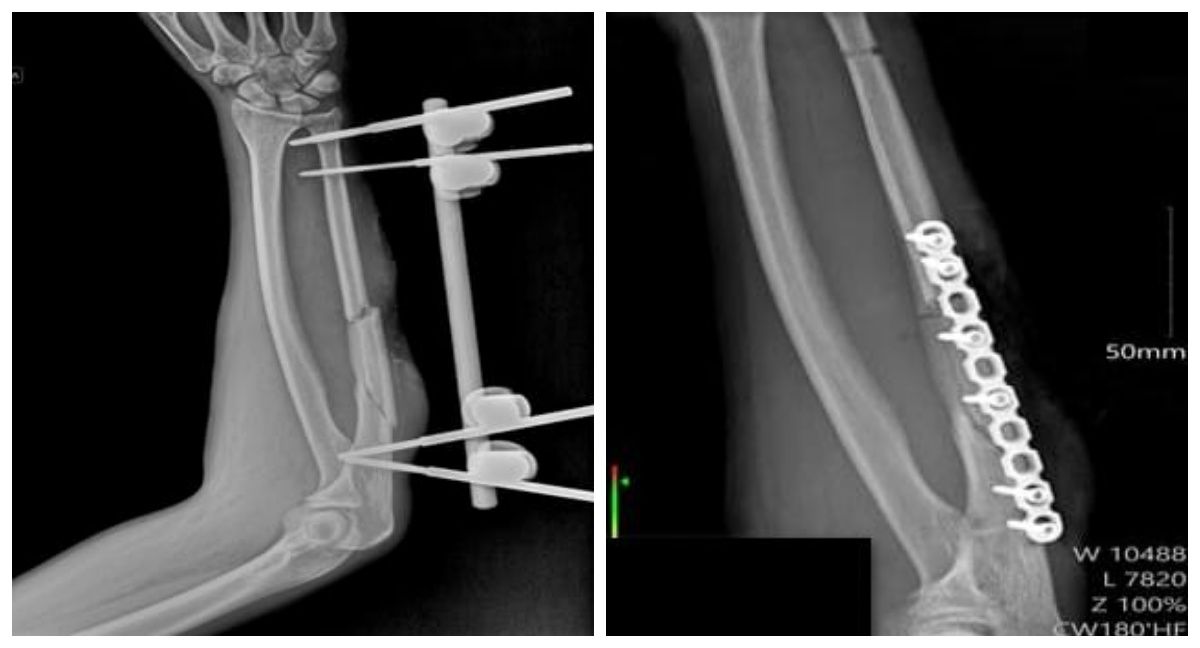

Врачи спасли воронежцу руку после сложного перелома